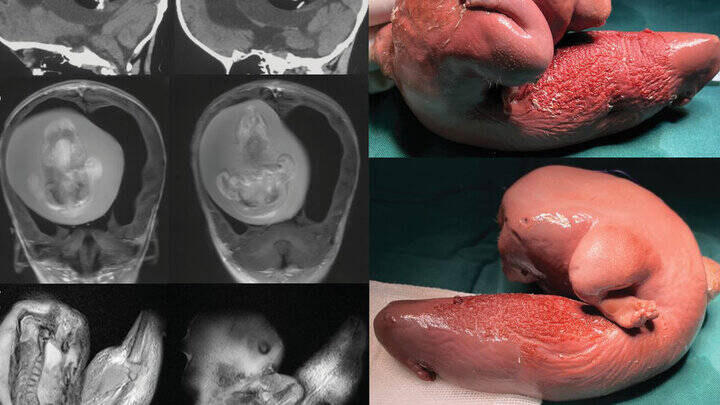

به گزارش مشرق، پزشکان دانشگاه فودان در شانگهای متوجه چند مشکل در یک دختربچه یک ساله مانند سر بیش از حد بزرگ و اختلال در مهارت های موتور حرکتی شدند. به نوشته نشریه IFLScience سی تی اسکن های سر این دختر بچه نشان داد مغز او تحت فشار است. علاوه بر آن تجمع مایعات سبب رشد بیش از اندازه در بطن های مغز شده بود.

محققان طی فرایند جراحی متوجه شدند رشد بطنی در حقیقت قل متولد نشده این کودک بوده است. هرچند بخش اعظم جنین تکامل نیافته بود اما به نظر می رسید اعضای بخش بالایی بدن و اندام های فرعی مانند انگشتان شکل گرفته اند.

چنین مواردی در متون پزشکی بسیار نادر هستند. موارد جنین داخل جنین در مراحل اولیه بارداری دوقلوها و زمانی اتفاق می افتد که بلاستوسیست( خوشه ای از سلول های در حال جدا شدن به وسیله تخمک بارور) به درستی انجام نمی شود.

در نتیجه این امر یکی از جنین ها دیگری را دربر می گیرد. هرچند باید اشاره کرد جنین دربرگرفته شده نمی میرد بلکه به دلیل خون رسانی منظم از قل دیگر، زنده می ماند اما رشد نمی کند.